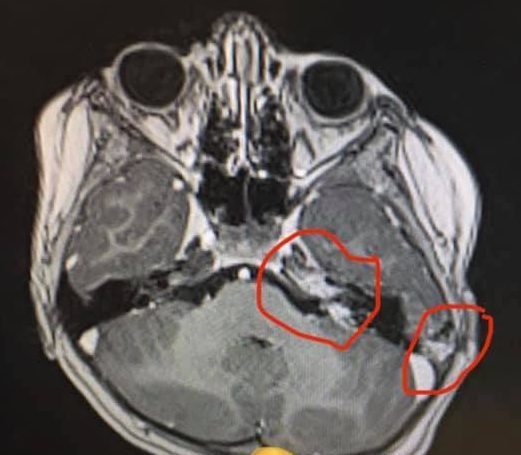

The infection then spread to her brain. She was taken to Wishaw where Ameilia was diagnosed with three abscesses in her brain after the CT scan results.

Jemma said: “Caused by a bacterial infection which probably entered her brain through the ear. She needed immediate treatment, but Wishaw was not equipped for this kind of condition.”